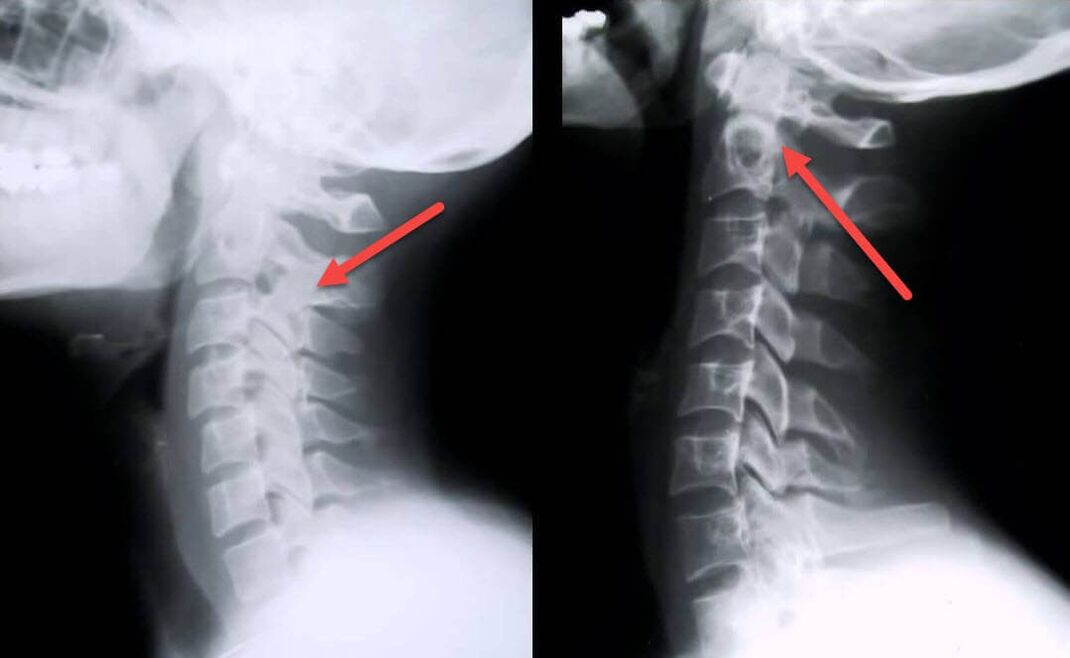

El procedimiento de diagnóstico más informativo es la radiografía. Las patologías de 1er grado corresponden a la 1ª o 2ª etapa radiológica. Las imágenes resultantes visualizan signos típicos de la enfermedad.

Etapas radiológicas de la osteocondrosis cervical de primer grado. Signos característicos

Etapa 1 Cambios menores en la curvatura de la columna en la región cervical, que afectan a uno o más segmentos.

Etapa 2 Ligero engrosamiento de los discos intervertebrales, deformación de las apófisis uncinadas, enderezamiento de la lordosis, crecimientos menores de las estructuras óseas.

Manifestaciones de osteocondrosis de la columna cervical en radiografía.